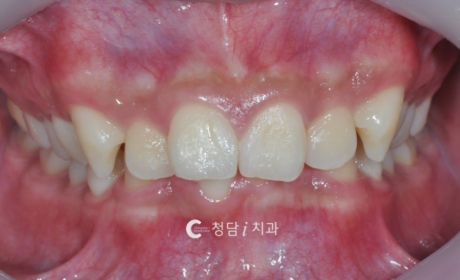

의정부 치아교정치과 청담i치과에서는 치열이 고르지 않고 덧니와 겹침이 심한 경우, 정밀 진단을 통해 발치 교정을 진행하고 있습니다. 다음 사례는 배열이 삐뚤빼뚤해 웃을 때 치아가 고르게 보이지 않던 환자분의 교정 전후 변화입니다. 교정 전에는 치아가 겹쳐 배열되어 스마일 라인이 고르지 않고, 웃을 때 치열이 복잡해 보이는 인상이었습니다. 공간 부족으로 인해 칫솔질이 어려워 구강 관리에도 불편함을 느끼고 […]